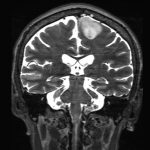

680

'25年10月

30代

小脳腫瘍

頭蓋内腫瘍摘出術

No.’25_82 手術前1

No.’25_82 手術前2

No.’25_82 摘出 前

No.’25_82  摘出 中

No.’25_82 摘出 後